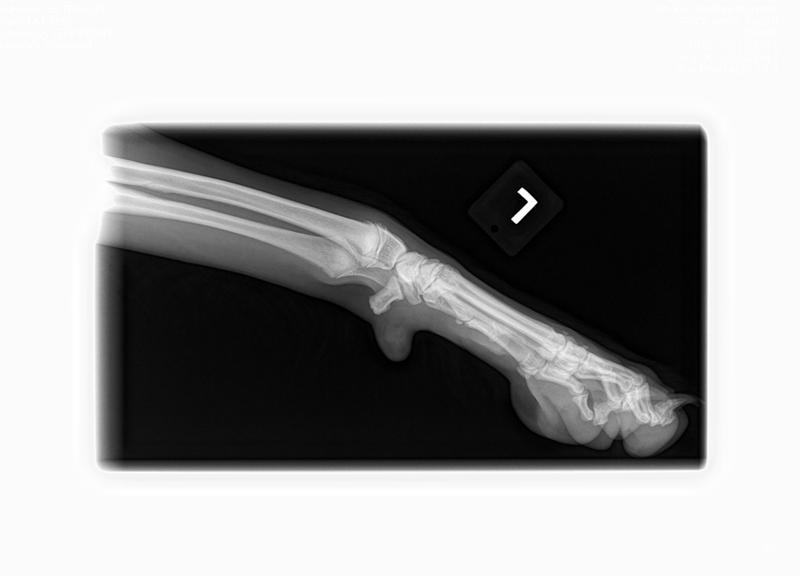

Here are BHRR's Spice's X-Rays: